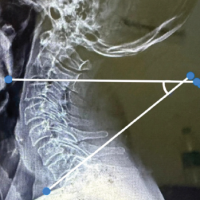

A 6-year-old school-going female child sustained trauma to the right forearm due to a fall on the outstretched hand, resulting in a closed injury in August 2021. Plain radiography of the elbow revealed right proximal ulna and radius fracture with radial head dislocation seen in (Fig. 1a). Although initially thought to be type IV Monteggia fracture, upon close observation, it was seen that the radius was fractured proximal to the ulna. Hence, as per Bado classification, it was diagnosed as a type I equivalent due to the radial head being dislocated anteriorly (Fig. 1b). The patient had a history of soft tissue injury around the elbow a year back, treated with plaster casting. The current fracture was treated within 48 h, where the radial and ulnar fractures were closed reduced and fixed with intramedullary titanium elastic nailing (TENS) system and the radiocapitellar joint was closed reduced and fixed with a K-wire. However, following surgery, it was observed that radiocapitellar joint was dislocated as seen in (Fig. 1c).

Figure 1: (a and b) Plain X-rays of the elbow showing proximal radius and ulna fracture with anterior dislocation of the radial head. As the radius is fractured proximal to the ulna, it is a type I equivalent under the Bado classification. (c) Post-operative X-ray showing persistent dislocation of radial head. (d) A single incision is made to expose both the radial head and the ulna shaft. The posterior interosseous nerve is identified. (e and f) The radio-capitellar joint is fixed to improve the rotational stability of the radius. (g) The wire is removed at 3 weeks, showing a stable joint. (h and i) At 3-year follow-up the elbow is stable, with limited pronation.

The ulna nail was removed. A single skin incision was taken to expose both the radiocapitellar joint and the ulna (Fig. 1d). In this case, the posterior interosseous nerve was identified as the proximal radius was fractured (Fig. 1e). The radiocapitellar joint was reduced. Ulna plating was done with a 3.5 mm dynamic compression plate giving a 10° posterior angulation to it. Just below the proximal physis in the radius, the TENS nail was advanced. Finally, the radiocapitellar joint was fixed with the elbow in 90° with a K-wire (Fig. 1f). With the use of an above-elbow slab, the limb was immobilized in full supination with elevation. The transcapitellar wire was removed at 3-week post-surgery (Fig. 1g). In 2024, at 3-year follow-up, the fracture was well reduced, with the patient having complete flexion at the elbow but with limited pronation (Fig. 1h and i).